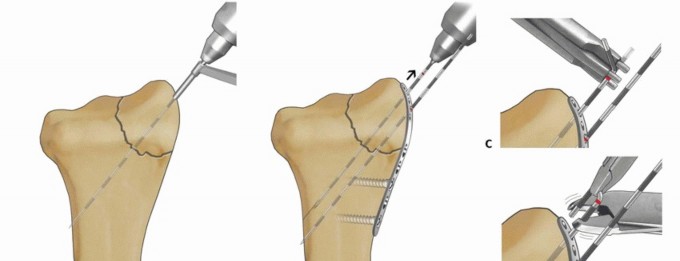

TECH FIG 8 • Radial column fixation with radial pin plate. A. Insertion of trans-styloid Kirschner wire. B,C.

TECH FIG 9 • Radial column fixation with fixed-angle radial column plate. A. Provisional placement of fixed-angle radial column plate. B. Drilling holes for distal fixed-angled pegs. C. Completed fixation. D. Unstable fracture injury films with segmental radial column comminution. E. Films 2 months postoperatively. Fixed-angle radial column support is used to avoid radial column shortening. Using fixed-angle drill guides, drill, measure, and insert locking fixation pegs of appropriate length into the distal fixed-angle holes in the plate and standard bone screws proximally into the shaft ( TECH FIG 9B-E).P.2873. Ulnar Corner and Dorsal Wall Fixation